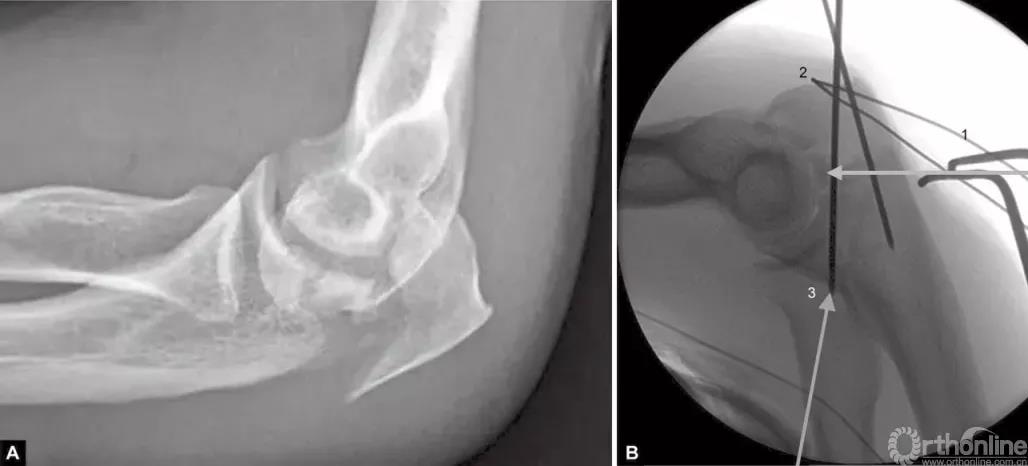

图1A~C(A)关节压缩骨折不易觉察,有经验的医生会注意到从冠状突到鹰嘴尖的关节间隙增宽而得出诊断;(B)如果没有的观察力,医生甚至会在术中X线片检查中都漏诊明显的压缩骨折。医生的注意力完全集中在检查植入物的位置上,因此容易忽略关节不一致;(C)术后摄片显示压缩骨折未复位

图2A~C关节面部分压缩非常不易觉察。有经验的医生会注意到鹰嘴曲线的变窄从而推断出压缩部分的存在。术中斜位X线片检查压缩骨折仍隐匿,仅在术后的X射线中越来越明显

图3A~C关节压缩骨折在鹰嘴斜位片中完全隐匿。在箭头的部位变窄可能是一个提示。如果不知道这种可能性,医生就会忽略该手术X线片检查中明显的关节面压缩骨折。术后标准的侧位片良好地显示了关节面压缩骨折。该医生未能完成最初的手术目标

当存在鹰嘴关节面部分压缩时,必须将其对应肱骨滑车抬高复位。在三头肌止点用钢丝牵开鹰嘴尖端(图4),复位压缩骨折,用细克氏针将其推靠在肱骨滑车上维持位置。克氏针必须紧贴压缩骨折部位的软骨下骨来维持位置。此时,用高质量的侧位X线片检查来确定压缩骨折的复位,克氏针的位置是否良好是非常必要的。另一种方法是采用松质骨植骨来支撑复位的压缩骨折。

图4A和B(1)将鹰嘴拉下复位关节内松动的骨片,用横向箭头所示细克氏针,将其推挤在滑车上维持复位;(2)钢丝环穿过三头肌止点周围将鹰嘴拉下;(3)克氏针紧贴软骨下骨插入支撑松动的关节内骨片(给向箭头所示克氏针)